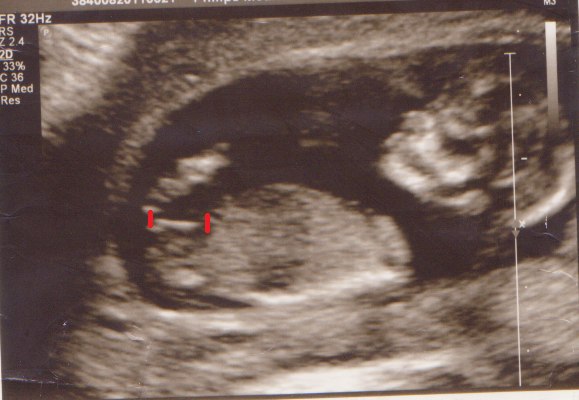

Hun undersøgte så de nedre dele og sagde, at både drenge og piger på nuværende tidspunkt har en "tap", og ud fra dens hældning, som hun sagde var meget lige, så mente hun, at det blev en pige

Har lige prøvet at indikere det hun vurderede udfra